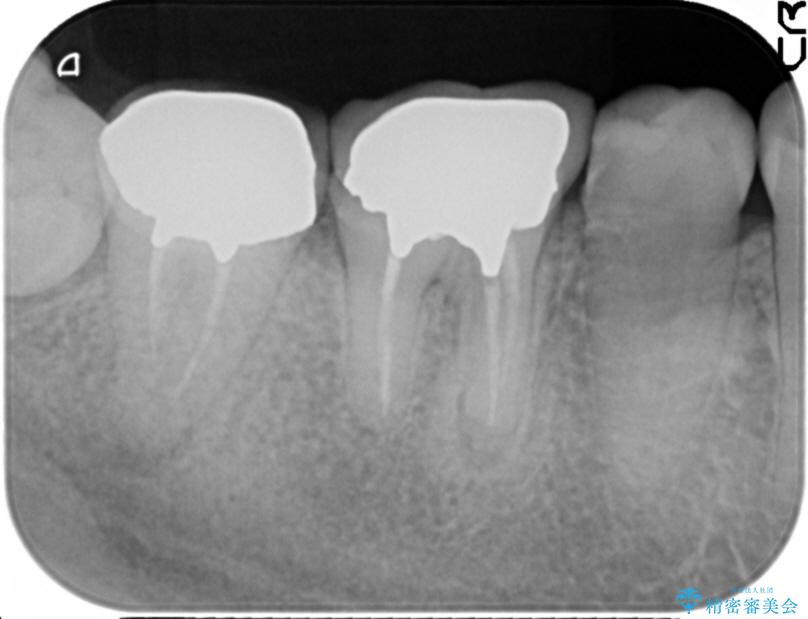

奥歯は既に根管治療が為されクラウンを装着する必要性がある状態ですが、歯の高さが低くクラウンの安定性・強度を担保するために歯周外科を行う治療計画としました。

歯周外科を行うことで、歯ぐきの位置を下げ歯の高さを作り出し安定したクラウンの装着が可能となります。また同時に舌の邪魔となっていた骨隆起の除去を行うこととしました。

- 37.4万円(ジルコニアクラウン×2・仮歯×2・歯周外科手術)費用は治療当時の料金となります